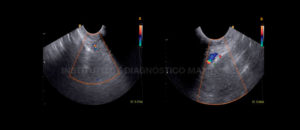

235 – Diagnóstico de sinusitis micótica maxilar con presencia de bola fúngica

DefiniciónLa sinusitis maxilar de origen odontogénico o dental, también conocida como sinusitis crónica de maxilar de origen dental, o sinusitis maxilar odontogénica, es una enfermedad